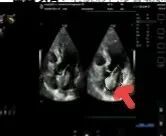

2025年深秋的一个清晨,82岁的马奶奶(化名)因持续胸闷气短被家人送至医院心内科。心脏超声检查显示,她的左心房内有一个直径近5厘米的肿瘤,随心跳规律摆动,如同一个随时可能破裂的“不定时炸弹”。更危急的是,冠脉造影进一步揭示其冠状动脉多支血管严重狭窄,左前降支狭窄达95%,回旋支中段完全闭塞,右冠状动脉弥漫性病变—两种致命性心脏疾病的叠加,让这位高龄患者的生命岌岌可危。

术前超声

术后超声